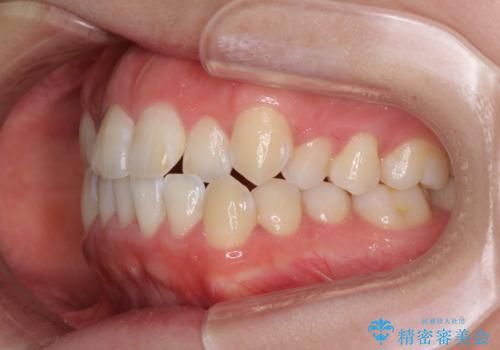

- 口元の突出感と口の閉じにくさ、前歯のデコボコを気にして来院された患者様です。

上下左右第一小臼歯4本を抜歯し、ワイヤー装置にて口元を引っ込めるよう矯正治療を行うこととしました。

骨格的に下顎骨が前方位にあるため、口元の突出感改善には限界があると思われましたが、唇の閉じにくさが改善するほど引っ込めることができました。